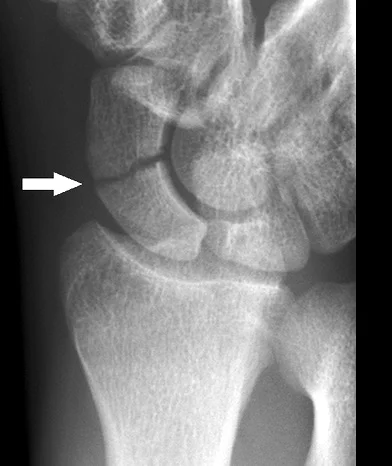

- Radiology:

- AP and Lateral not enough

- Need an special scaphoid view